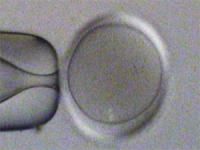

透明帯から孵化(ハッチング)中の胚 孵化後の胚